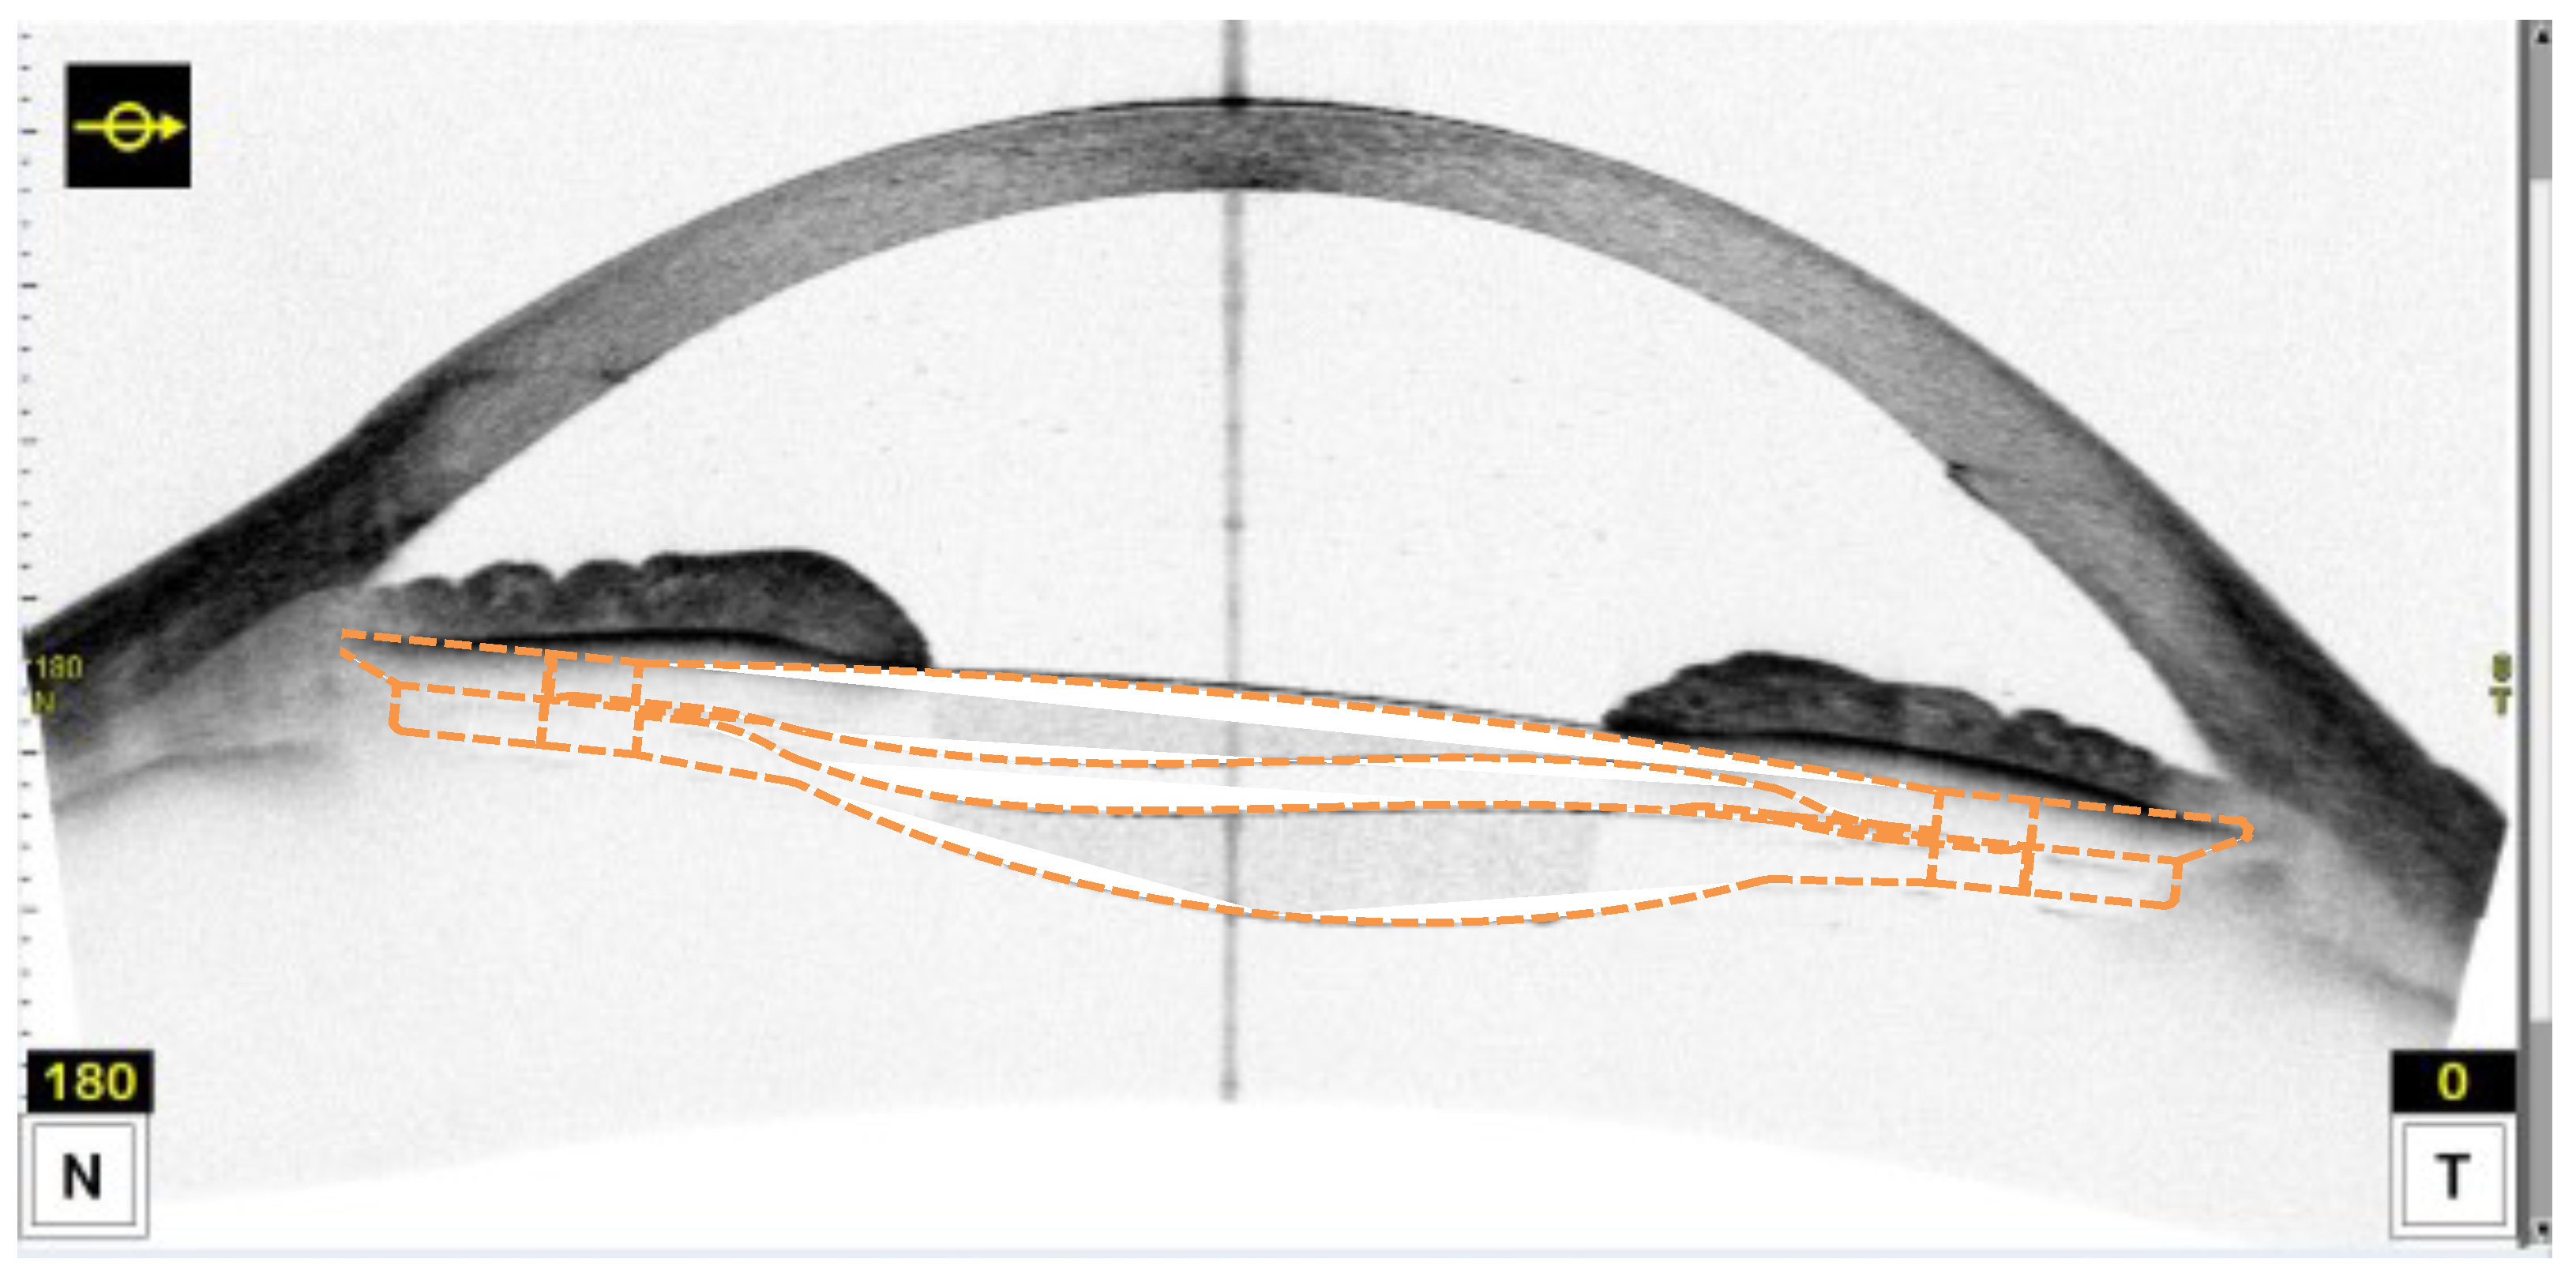

- Piñero, D.P.; Puche, A.B.P.; Alió, J.L. Ciliary sulcus diameter and two anterior chamber parameters measured by optical coherence tomography and VHF ultrasound. J. Refract. Surg. 2009, 25, 1017–1025. [Google Scholar] [CrossRef] [PubMed]

- Dong, J.; Yao, J.; Chang, S.; Kanclerz, P.; Khoramnia, R.; Wang, X. Evaluation of Ocular Diameter Parameters Using Swept-Source Optical Coherence Tomography. Medicina 2023, 59, 899. [Google Scholar] [CrossRef]

- Naujokaitis, T.; Auffarth, G.U.; Łabuz, G.; Kessler, L.J.; Khoramnia, R. Diagnostic Techniques to Increase the Safety of Phakic Intraocular Lenses. Diagnostics 2023, 13, 2503. [Google Scholar] [CrossRef]